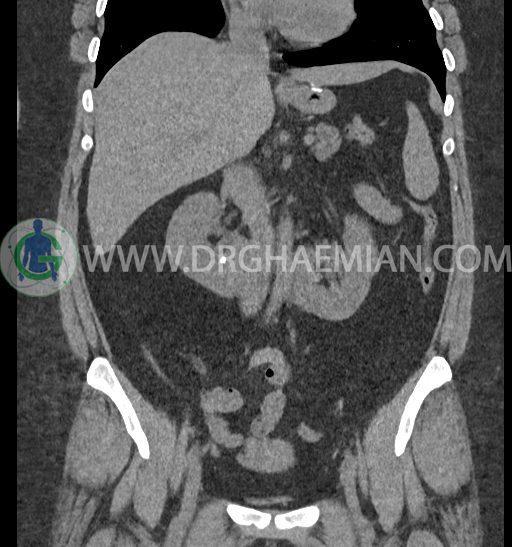

سی تی اسکن شکم و لگن با استفاده از اشعات ایکس تصاویر عرضی از ناحیه شکم و لگن ایجاد میکند. در این کیس کلیه نعل اسبی و سنگ کلیه مشاهده می شود.

در سی تی اسکن اسپیرال شکم و لگن بدون کنتراست (مولتی دیدکتور 16 با مقاطع ظریف و بازسازی های ساژیتال و کرونال) :

-horseshoe kidney

-حداقل سه سنگ 5mm در کلیه راست و یک سنگ 3mm در کلیه چپ بدون شواهدی از هیدرونفروز

-آپاندیس نرمال بصورت رتروسکال

مشهود است.